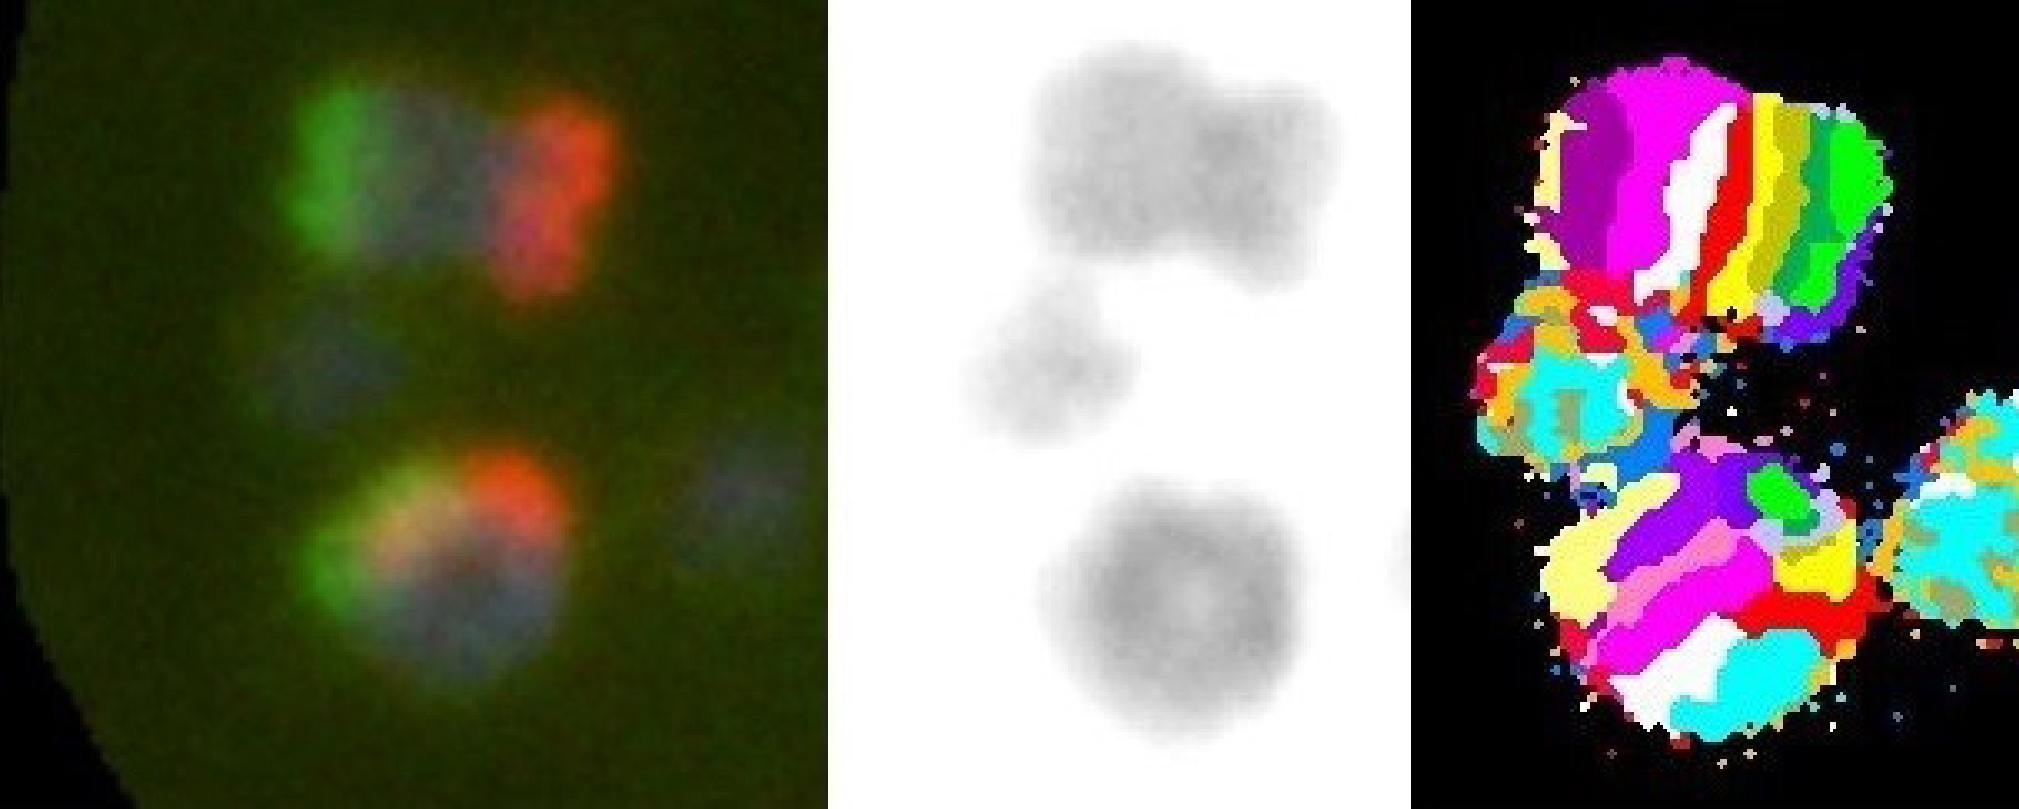

Метод mBAND (multicolor banding) основан на гибридизации частей хромосомы зондами, меченых различными флуорохромами, вдоль длины хромосомы, таким образом, что зонды гибридизуются частично перекрываясь на отдельных участках хромосом. Характерная многоцветная полосчатая картина mBAND создаётся путём количественной оценки соотношения интенсивности флуоресценции вдоль хромосомы. Эти соотношения уникальны и визуализируются в виде псевдоцветов, специфичных для каждой полосы (рис. 1). mBAND предоставляет информацию, которая позволяет проводить точный анализ даже очень сложных меж- и внутрихромосомных аберраций1.

Рис. 1. Схема гибридизации зондов для Х-хромосомы: спектры возбуждения флуорохромов сопоставимы с аквамариновым, зелёным, оранжевым, красным и ближним инфракрасным спектром (XCyte 1. Human mBAND Probe. https://metasystems-probes.com/en/probes/mband/d-0201-030-di).

Fig. 1. Scheme of probe hybridization for X-chromosome:excitation/absorption spectra of fluorochromes are comparable to the aquamarine, green, orange, red and near-infrared spectrum/spectra (XCyte 1. Human mBAND Probe. https://metasystems-probes.com/en/probes/mband/d-0201-030-di).

Работа с оцифрованными изображениями проводилась с помощью программного обеспечения Isis (Metasystems, Германия). Для исследования выбирали метафазы, содержащие Х-хромосомы без артефактов. Анализировали Х-хромосомы в соответствии с расположением спектров возбуждения флюорохромов, как показано на рис. 1. На рис. 2 представлены Х-хромосомы, окрашенные методом mBAND (без аберраций).

Рис. 2. Х-хромосомы, окрашенные методом mBAND (норма).

Fig. 2. X-chromosomes stained with mBAND (norm).